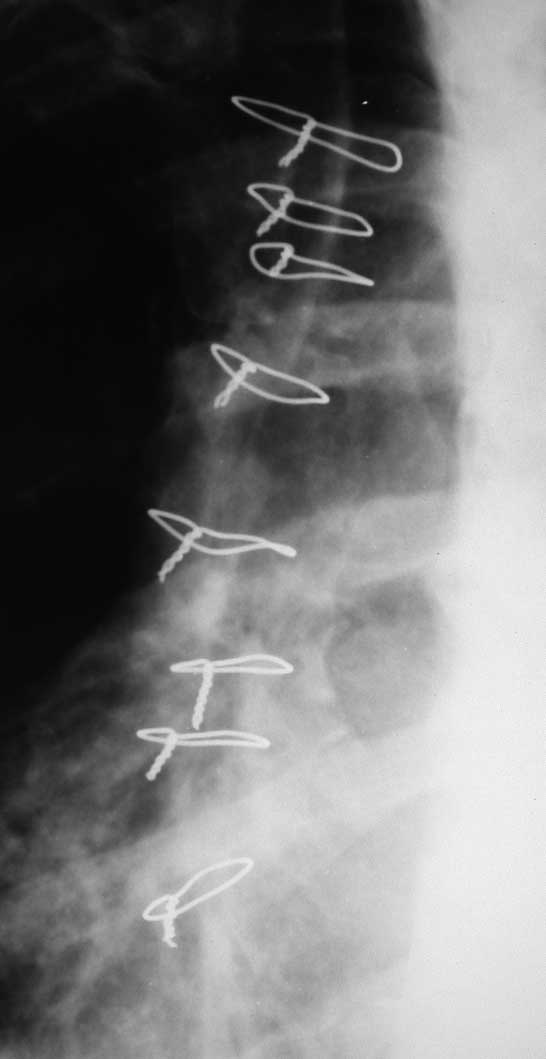

В 2010 г. проведено АКШ,  доступ через грудину, затем остеосинтез проволокой. Беспокоят боли в области грудины усиливающиеся при движениях и экскурсии грудной клетки. Признаков воспаления в области грудины нет. При пальпации проволока не определяется, дефект грудины хорошо ощутим. Подвижность отломков грудины минимальная.

4.	Остеосинтез смоделированными 2 пяточными пластинами LCP

Имя     : DSCN4611.JPG